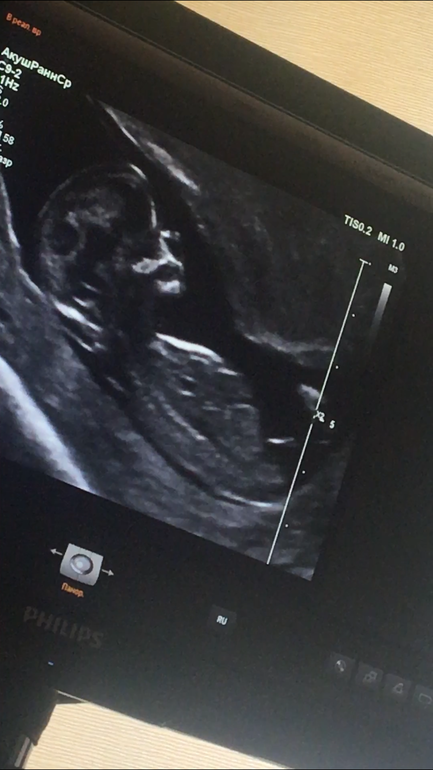

Наш первый скрининг 😍❤️ И пол крохи 😏

Результаты: УЗИ, КТГ, доплера, скринингаВот и прошли мы первый скрининг 😍 страха было..полные штаны 😂😂 но все просто идеально 😍🙏 врач раза три повторил что у меня и у ребёнка все хорошо 😂😂как будто понимал,что мне не верится 😂

теперь вопросик к вам девчонки,кто шарит в УЗИ и может распознать пол 😏 врач конечно же сам заговорил на эту тему,потому что не смотря на маленький срок он почти со стапроцентной уверенностью сказал пол 🙈 но я хочу у вас поинтересоваться))правда на столько видно?и кто же в теремочке живёт?😍